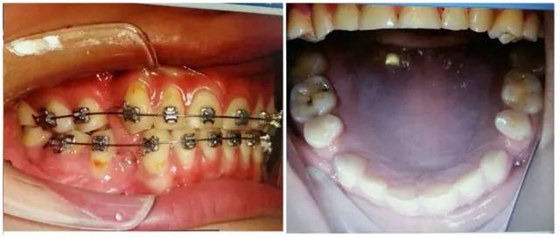

(以下為治療后的照片:患者癥狀得到了良好改善。)

足以看出,尖牙保護(hù)(牙合)在臨床工作中的重要作用,它是以尖牙為支撐,對其他牙齒起到保護(hù)作用。其特點(diǎn)是正中關(guān)系(牙合)與正中(牙合)協(xié)調(diào);側(cè)方咬合運(yùn)動時,工作側(cè)只有尖牙保持接觸非工作側(cè)牙齒不接觸;在作前伸咬合運(yùn)動時,上下頜前牙切緣相對接觸,后牙不接觸。尖牙具有適合制導(dǎo)的舌面形態(tài),可使用(牙合)力趨于軸向;牙根長且粗大,支持力強(qiáng);尖牙位居牙弓前部,在咀嚼時構(gòu)成第Ⅲ類杠桿,能抵御較大的咀嚼力;以及尖牙牙周膜感受器豐富,對刺激敏感,能及時調(diào)整反應(yīng)都是尖牙的有利條件。尖牙形態(tài)的恢復(fù)在此例正畸治療中,對前牙、后牙都起到了很好的保護(hù)作用,也能保證后期按照標(biāo)準(zhǔn)(牙合)進(jìn)行(牙合)重建時后牙無干擾。功能在先,美觀在后,權(quán)老師為您展示了這樣的治療理念。

要想成為一個合格的(牙合)學(xué)醫(yī)生,僅僅局限于處理患者已經(jīng)出現(xiàn)的問題是遠(yuǎn)遠(yuǎn)不夠的,善于挖掘患者潛在隱患的醫(yī)生才是合格的,細(xì)致入微的權(quán)老師還在病例中發(fā)現(xiàn)兩個潛在問題,群里的同仁們,來吧,跟著權(quán)老師,看圖說問題。